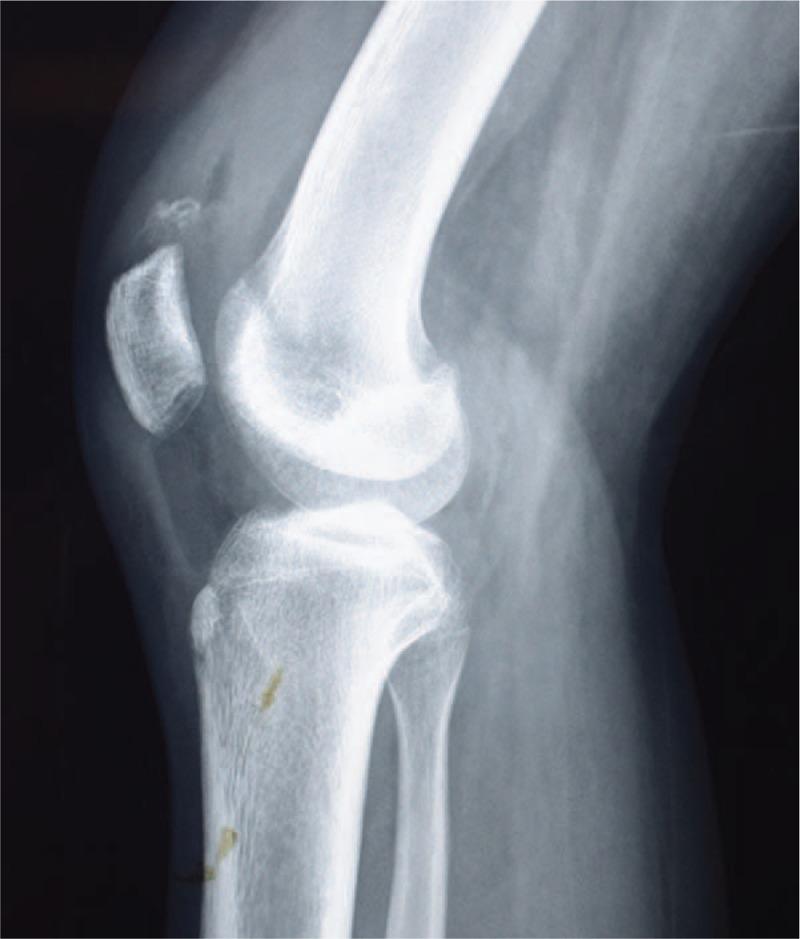

We present a rare case of a 15-year-old girl who suffered a sleeve fracture at the superior pole of the right patella. The patient had a history of dislocation of the patella 2 weeks ago. Physical examination showed tenderness on palpation over the upper pole of the patella and absence of active movement of the knee accompanied by swelling and joint effusion. A plain radiograph showed an avulsed fragment of the superior pole of the patella.

Magnetic resonance imaging showed a superior pole patellar avulsion fracture and dysfunction of the knee extensor mechanism.